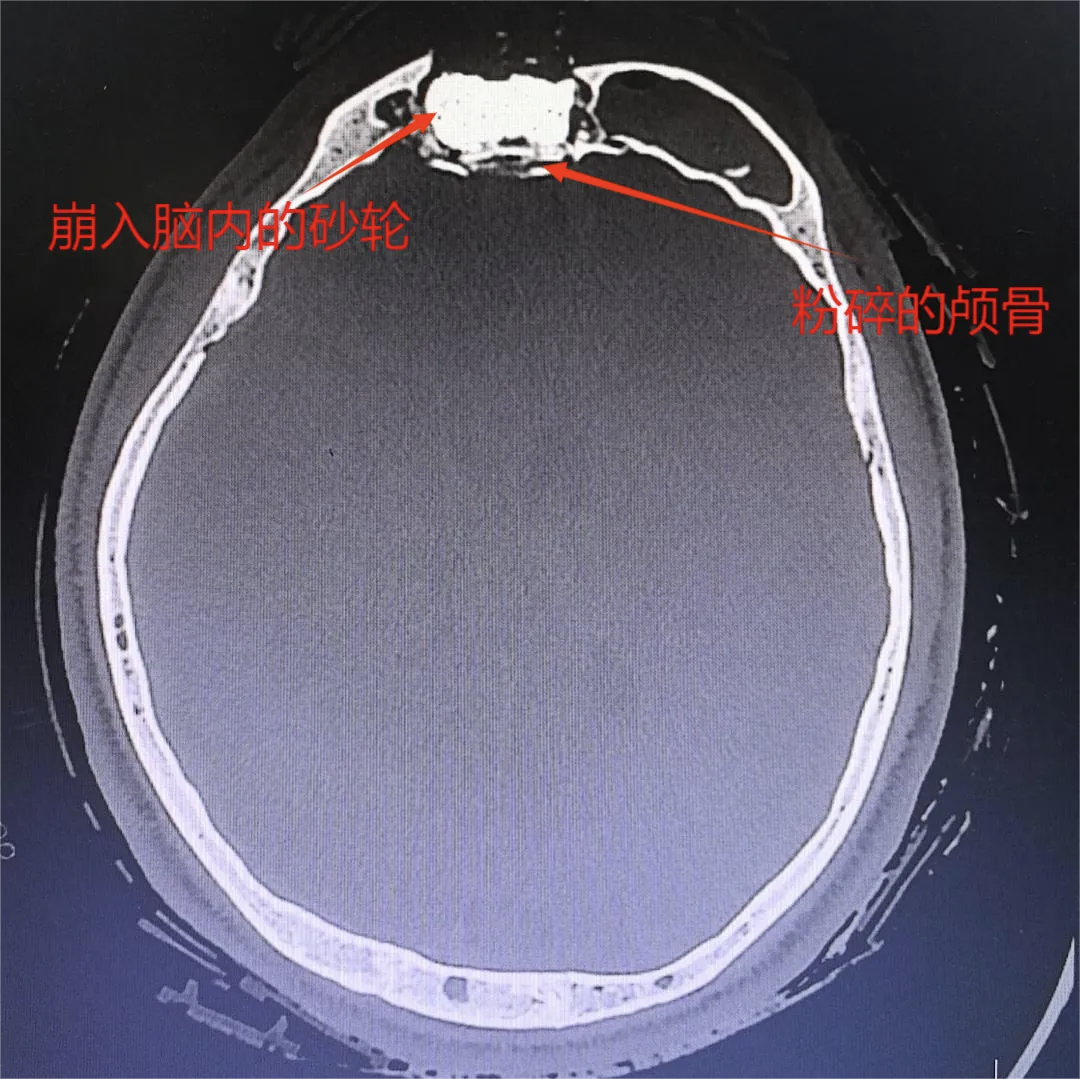

头部CT检查结果传来,伤情比预想中更为严峻,砂轮碎片面积不小,不仅穿透额骨,还深深嵌入脑内。颅内堆积的大量血肿已导致脑组织受压,中线明显偏移。额窦与鼻骨也出现粉碎性骨折。